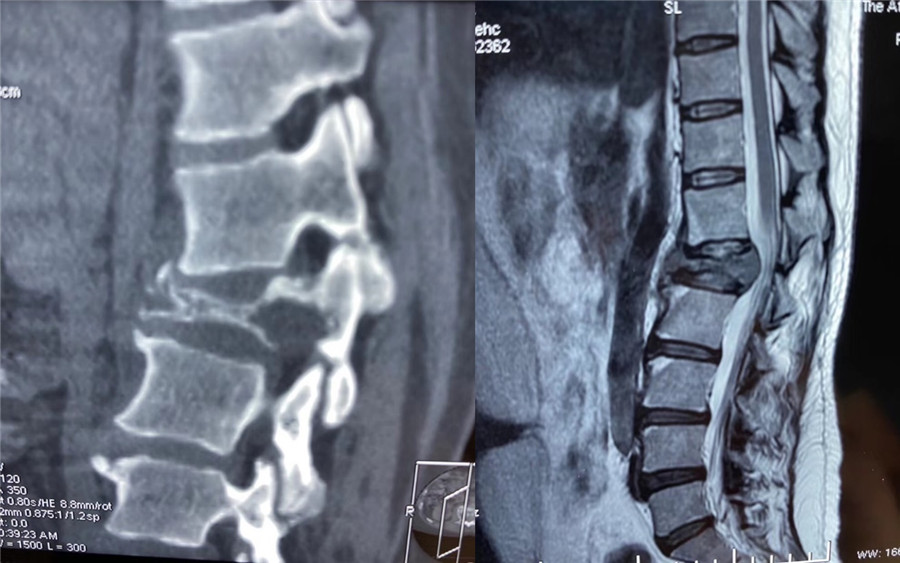

近日,我院脊柱外科赵岩团队收治一名因腰背痛并逐渐加重的患者,该患者4年前因乳腺癌行保乳手术治疗,后因经济原因未进一步作放化疗,此次详细辅助检查后高度怀疑为腰1椎体转移瘤,肿瘤椎体及附件骨质已被严重侵蚀,随时会有脊髓被进一步压迫而导致患者瘫痪的可能。

该患者家庭经济拮据,且疫情期间无法外请北京专家前来手术,患者及家属辗转自治区多家医院找到赵岩医生,赵岩团队经过反复讨论和充分准备,最终在麻醉科(手术室)紧密配合下独立完成一期后路固定+En-bloc腰1椎体肿瘤切除术+椎体重建术,该手术首先行后路脊柱固定,其次从后方经椎弓根将病变节段的后部结构整块切除,再向前方分离骨膜和椎体周围血管(这是手术风险最大的步骤),分离彻底后将椎体一并整块切除,最后重建脊柱前中柱。

术前